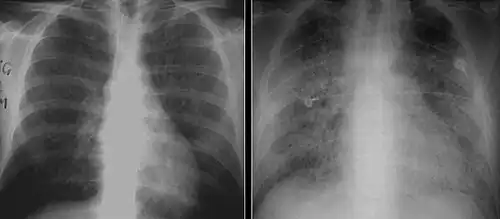

X-ray and CT of ground glass opacities and pneumothorax in pneumocystis pneumonia.[7]

Pneumothorax is a well-known complication of PCP.[8] Also, a condition similar to acute respiratory distress syndrome (ARDS) may occur in patients with severe Pneumocystis pneumonia, and such individuals may require intubation.[9]